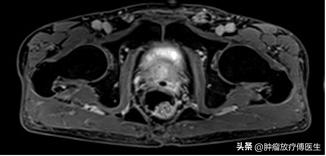

患者,男,76岁。2015年10月于外院体检发现前列腺特异性抗原(prostate specific antigen,PSA):19ng/ml,2015年10月21日就诊于我院泌尿外科,查PSA 17.590ng/ml;盆腔磁共振(MRI)示(图1)前列腺体积稍大,大小约4.7cm×3.1cm×3.6cm,左侧外周叶内可见结节样异常信号影,大小约2.2cm×1.6cm,边界欠清,考虑前列腺癌。全身骨显像未见异常。2015年10月26日行前列腺穿刺病理活检示(图1-2)(左外腺)前列腺增生症,局灶低级PIN,(右外腺)前列腺增生症,背景中见小灶高分化前列腺腺泡细胞癌,Gleason评分3+2=5。

图1 2015年10月23日放射治疗前盆腔MRI